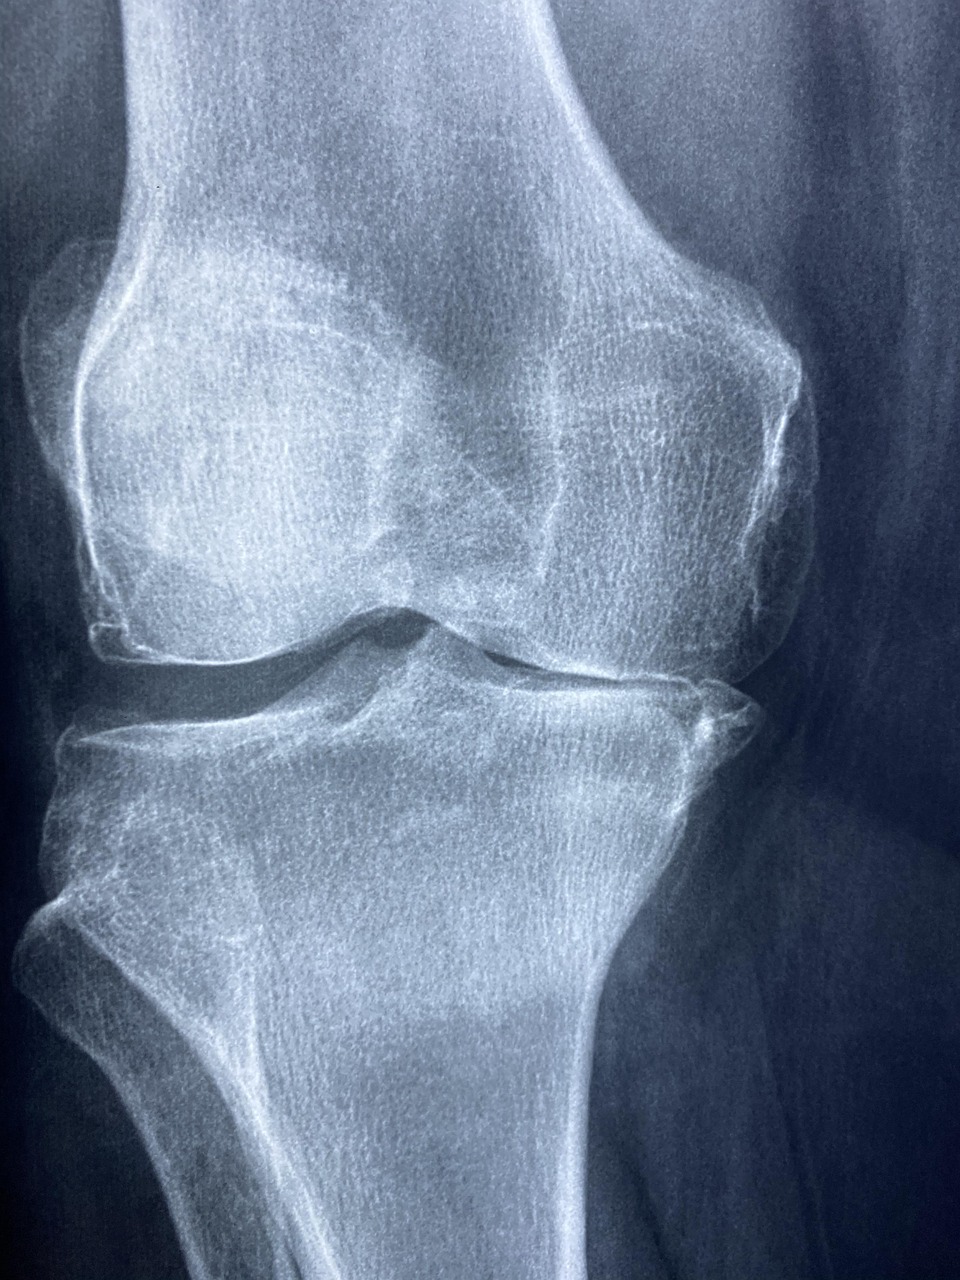

- Diagnostik mit bildgebenden Verfahren (z. B. Röntgen, MRT, Ultraschall)